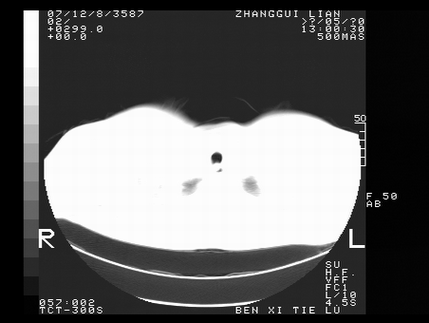

标题: CT10817:女,46,胸疼,无其他病史 [打印本页]

标题: CT10817:女,46,胸疼,无其他病史

首先考虑左侧中央型肺癌伴阻塞性肺炎、纵隔内、弓旁淋巴结转移可能性大(纵隔窗调的欠佳)

1 左侧中央型肺癌伴阻塞性肺炎 2 左肺门及纵隔淋巴结转移!3两侧胸腔及心包积液.

左肺中央型肺癌伴左肺上叶阻塞性肺炎两侧胸腔积液纵隔窗不清楚

3两侧胸腔及心包积液.